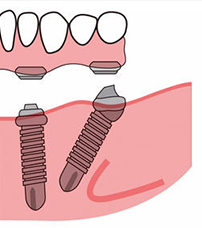

2、术后2小时后(麻醉消散后)是可以吃流食的,虽然说是拔牙即刻用,但其实种植体和牙槽骨没有愈合好,太硬的食物肯定会松脱的,温度也要适宜,你们可以看下图,种植体植入后,还需要基台和临时冠,没有稳固结合的种植牙,吃不了硬物。